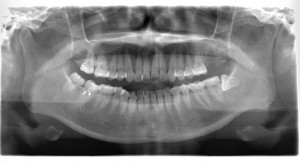

左上の第2大臼歯(写真では向かって一番右上)の欠損部に、右下第3大臼歯(親知らず)(写真では向かって一番左下)を移植します。